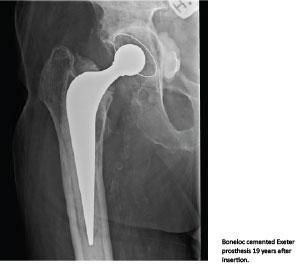

Conclusion: This study provides the first long-term results on Boneloc-cemented primary hip arthroplasty. The Exeter prosthesis, especially the stem, maintains the previously published acceptable survival and results despite the documented inferior quality of the cement.

Boneloc (methylmethacrylate/decylmethacrylate/isobornylmethacrylate) bone cement was developed to decrease polymerisation heat and leakage of toxic methyl methacrylate monomer to the adjacent bone while preserving its mechanical properties [1]. Furthermore, the unique closed mixing- and delivery system prevented release of possible toxic vapours to the operation theatre, which was an important reason motivating the introduction of Boneloc into many Danish orthopaedic departments. However, within a few years, alarming aseptic loosening rates were reported which were probably caused by a significantly reduced tensile strength and Young’s modulus compared with contemporary cement brands [2, 3]. Only the Exeter stem (collarless, double tapered and highly polished) has shown acceptable short- to mid-term aseptic loosening rates [4], although results were inferior to those observed for the same stem fixated with high viscosity cement [5]. In Scandinavia, Boneloc was declared a surgical catastrophe, and the cement was withdrawn from the market in 1995. In Denmark, special patient insurance legislation was passed in 1999 concerning economic compensation to patients with health-related consequences after operation with Boneloc cement.

After 18-20 years, Boneloc-cemented primary Exeter hip arthroplasty still shows a good clinical result and acceptable prosthetic survival. With a revision rate of 0.5%/year, the polished, collarless, double-tapered stem concept once again has proved its versatility, adaptability and durability after 40 years on the orthopaedic market.